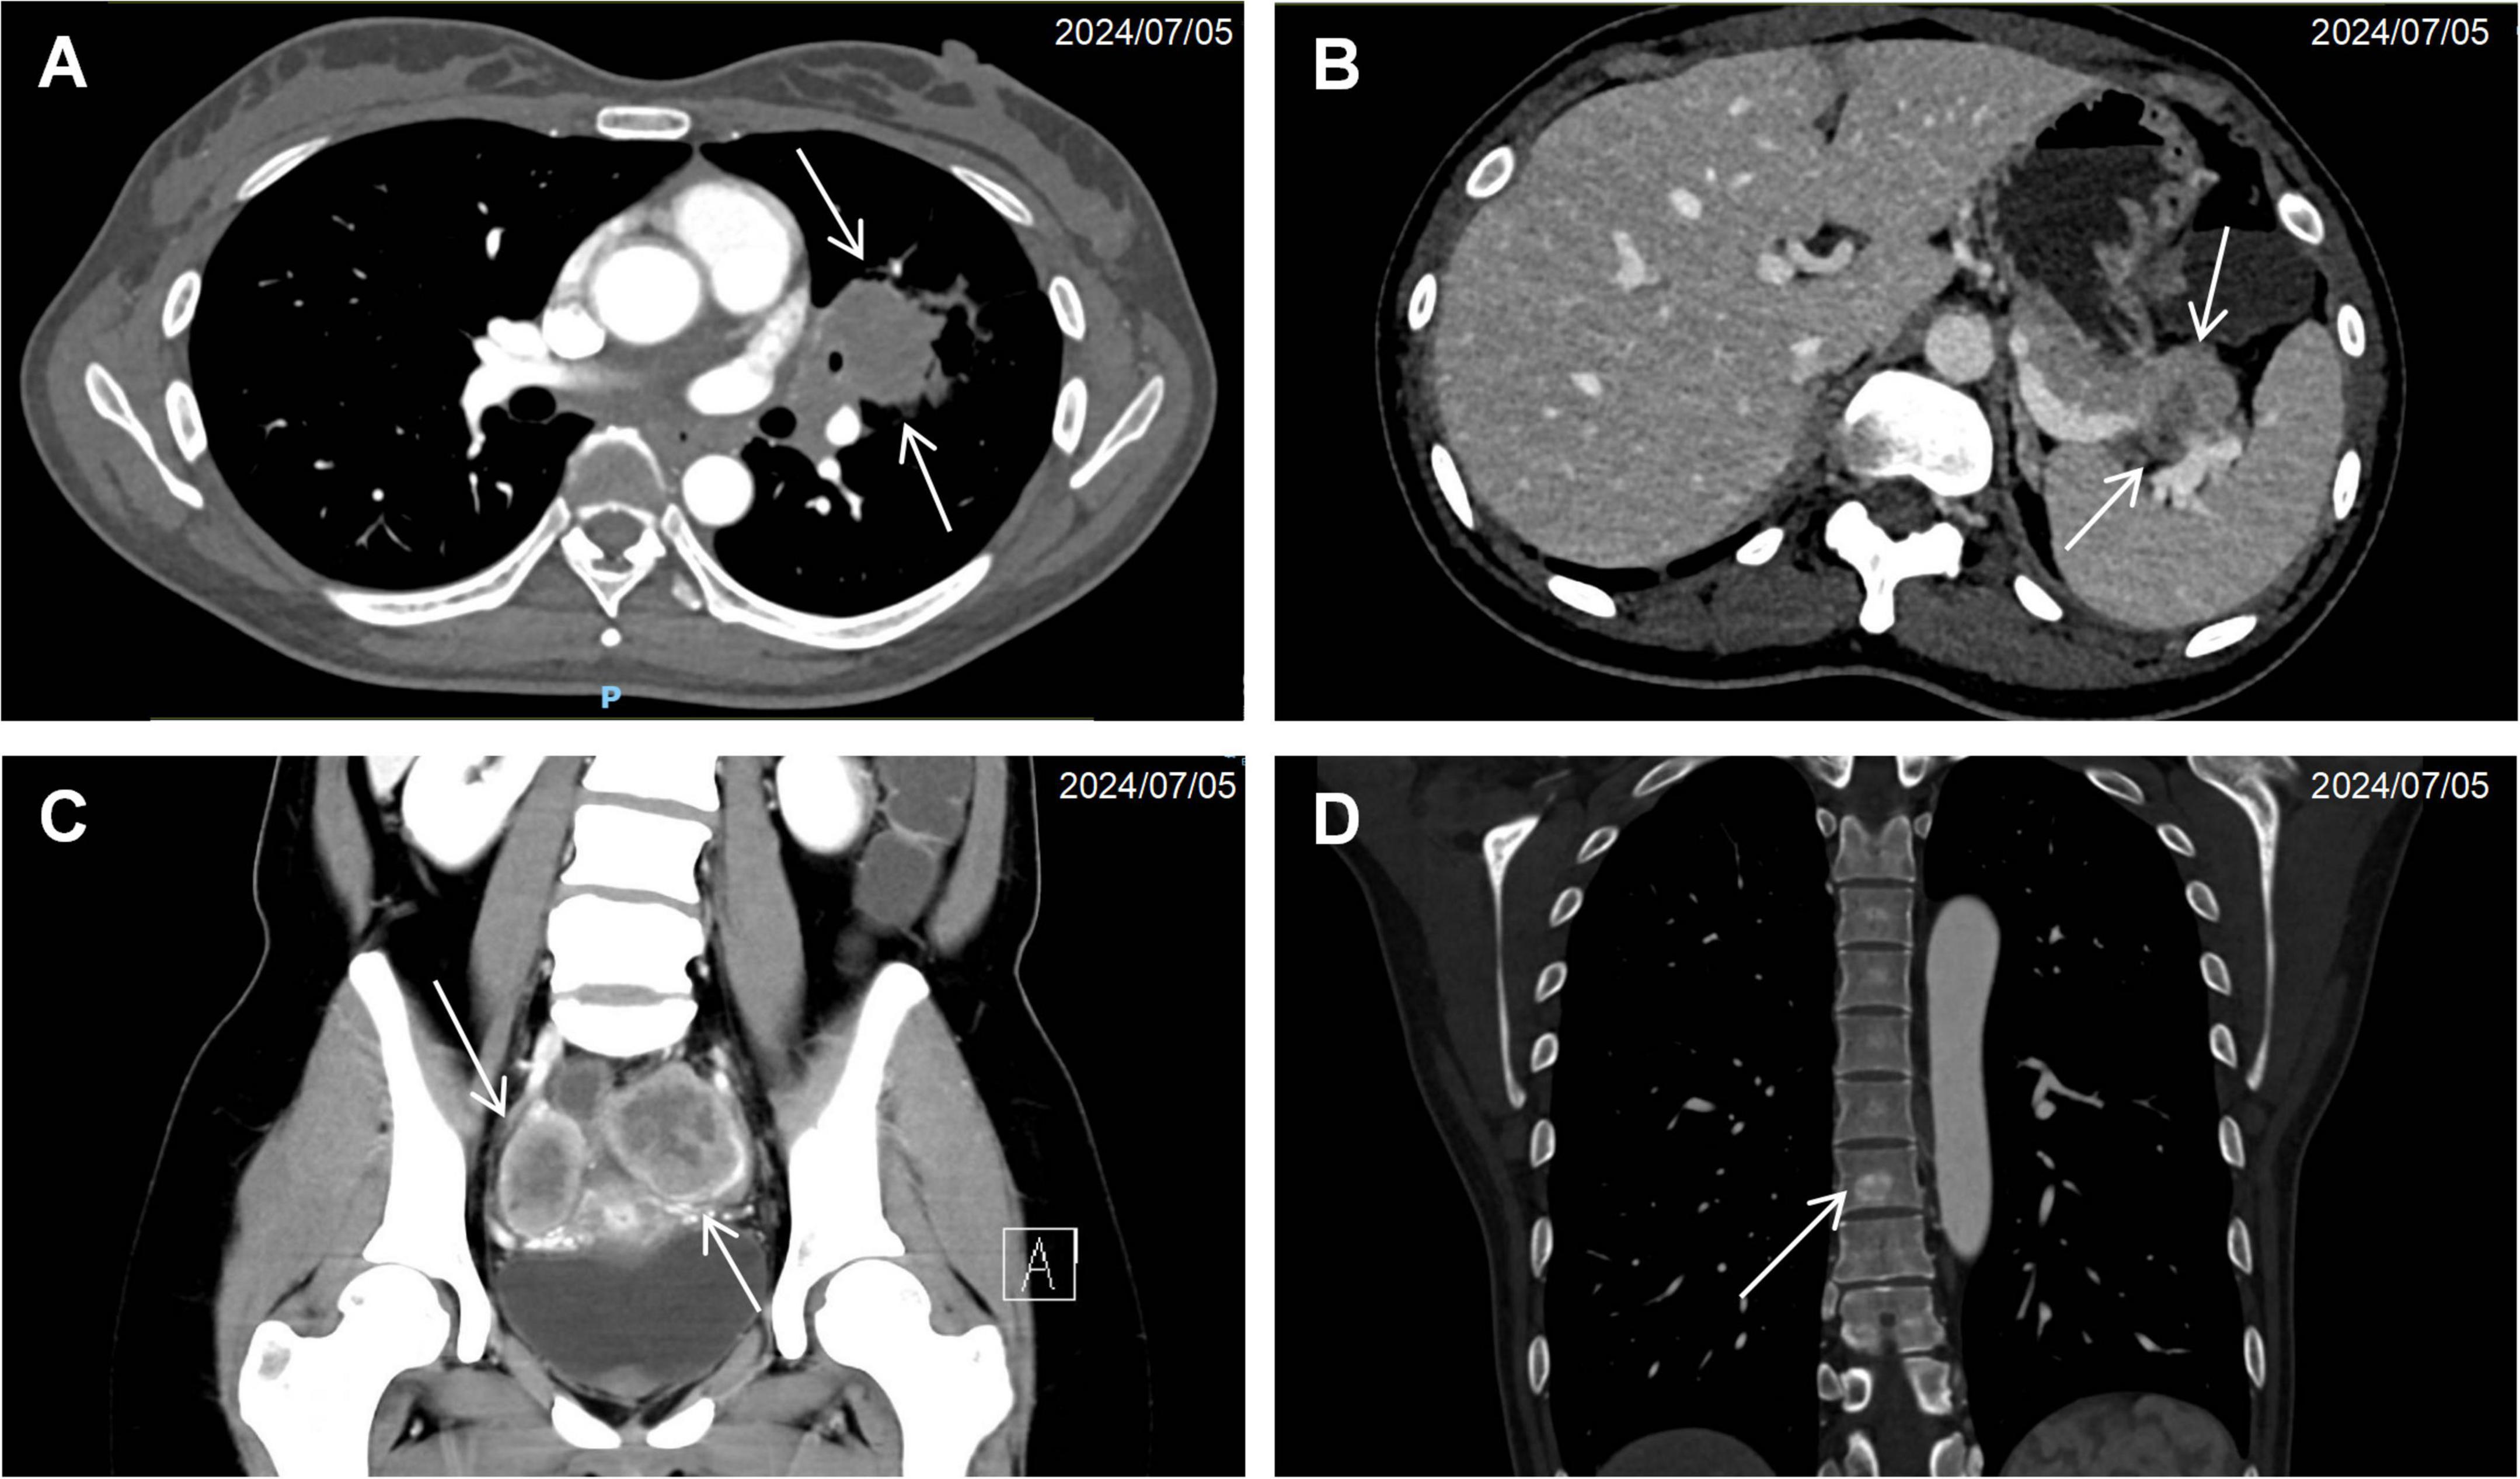

Computed tomography of the chest, abdomen, and pelvis revealed multifocal lesions involving the left lung, pancreas, appendix, and bilateral adnexa (Figure 1). A solid left upper lobe mass (40 × 34 × 46 mm) demonstrated heterogeneous enhancement with bronchial cutoff and pleural indentation. Pancreatic lesions included hypodense masses in the uncinate process (20 mm × 18 mm; progressive enhancement) and tail (28 mm × 22 mm; heterogeneous enhancement). An appendiceal nodule (13 mm × 9 mm) showed uniform enhancement with ileocecal lymphadenopathy. Complex cystic-solid adnexal lesions were observed, largest in the left ovary (55 × 52 × 52 mm). Differential diagnosis included primary lung adenocarcinoma and NET, with additional lesions noted in the thyroid, left breast, and T8/L5 vertebrae. Magnetic resonance imaging (MRI) of the chest and abdomen confirmed multi-organ involvement (left lung, pancreas, bilateral adnexa) with iso- to hyperintense signals. Vertebral MRI demonstrated a T8 nodule (14 mm × 8 mm) with long T1/T2 signals. Cranial MRI showed normal pituitary architecture but abnormal foci in cerebellar hemispheres, left temporal lobe, and right frontal lobe, the largest (4 mm) in the left frontal lobe (Figure 2). Thyroid ultrasound revealed C-TIRADS 4A nodules, with the largest measuring 29 × 22 × 15 mm and showing heterogeneous enhancement on contrast-enhanced ultrasound.

FIGURE 1

Cross-sectional imaging findings of neuroendocrine neoplasms. (A) Contrast-enhanced CT demonstrating a solid pulmonary mass (arrow) in the left upper lobe with associated bronchial truncation. (B) Hypodense pancreatic tail lesion (arrow) exhibiting ill-defined margins and poor demarcation from adjacent pancreatic parenchyma. (C) Bilateral adnexal complex cystic-solid lesions (arrow). (D) Anodular hyperdense lesion (arrow) within the T8 vertebral body.